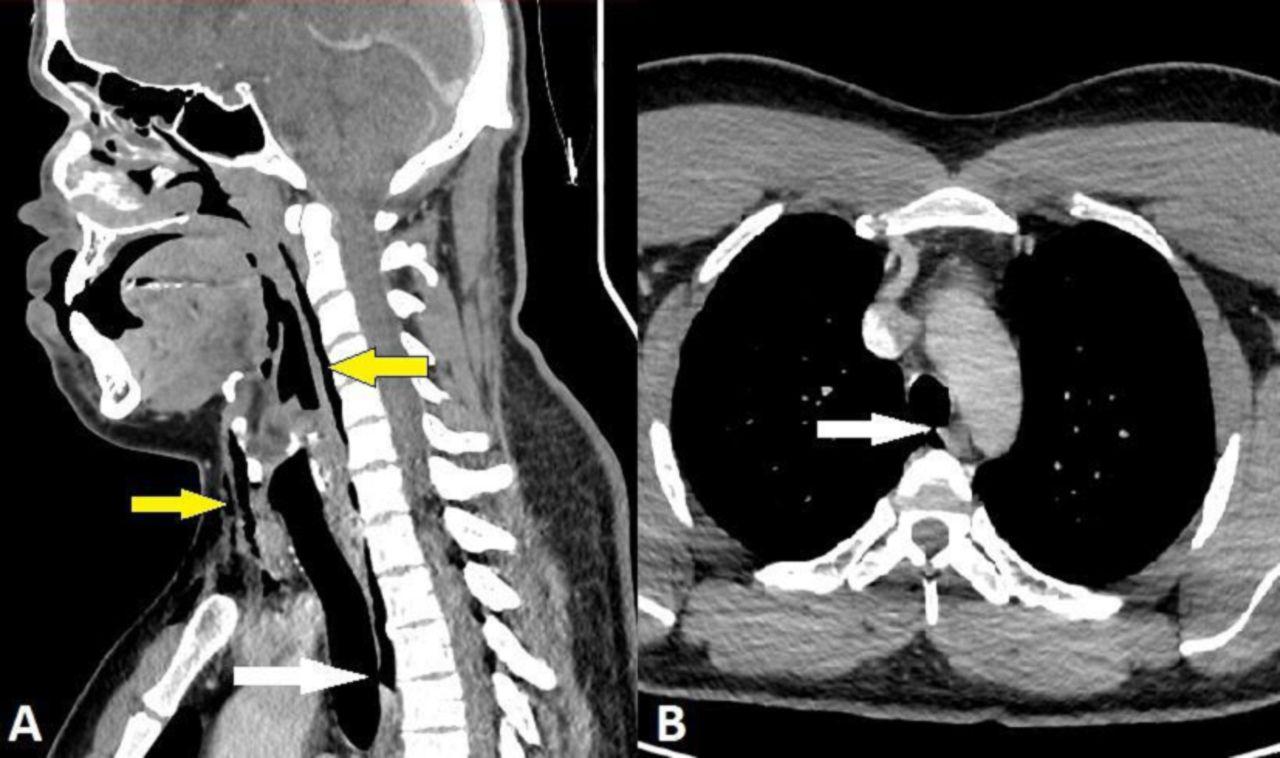

經過X光檢查及電腦掃描後發現,男子的第三和第四節頸椎之間有一處2毫米乘2毫米乘5毫米的氣管撕裂,還有縱膈腔氣腫和頸部手術性肺氣腫,所幸不危及生命,亦不用做手術。男子接受止痛藥和花粉症藥物治療,留院觀察48小時後出院,醫生提醒他兩周內不要有任何劇烈運動。他5周後再接受檢查,顯示氣管撕裂已完全癒合。